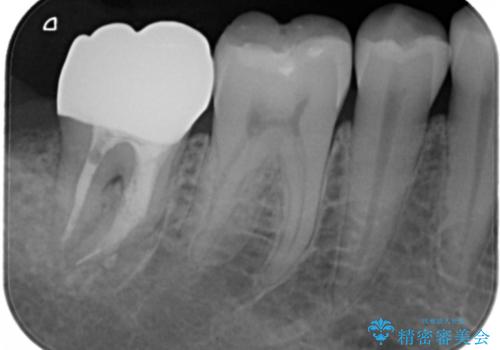

- 過去に他院で治療した部位が材料劣化を起こしていたため、セラミック治療を希望された患者様です。

切削量を考慮し、セラミックインレーを選択しました。

虫歯が深かったので、CRを詰めた上で形態を整えています。